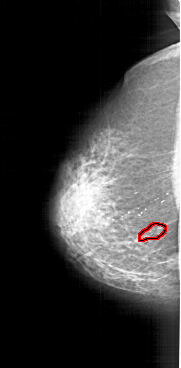

A_1123_1.LEFT_MLO

LEFT_MLO LINES 6751 PIXELS_PER_LINE 3181 BITS_PER_PIXEL 12 RESOLUTION 43.5 OVERLAY

FILE: A_1123_1.LEFT_MLO.OVERLAY

TOTAL_ABNORMALITIES 1

ABNORMALITY 1

LESION_TYPE CALCIFICATION TYPE PLEOMORPHIC DISTRIBUTION SEGMENTAL

LESION_TYPE MASS SHAPE LOBULATED MARGINS ILL_DEFINED

ASSESSMENT 4

SUBTLETY 4

PATHOLOGY BENIGN

TOTAL_OUTLINES 1

BOUNDARY